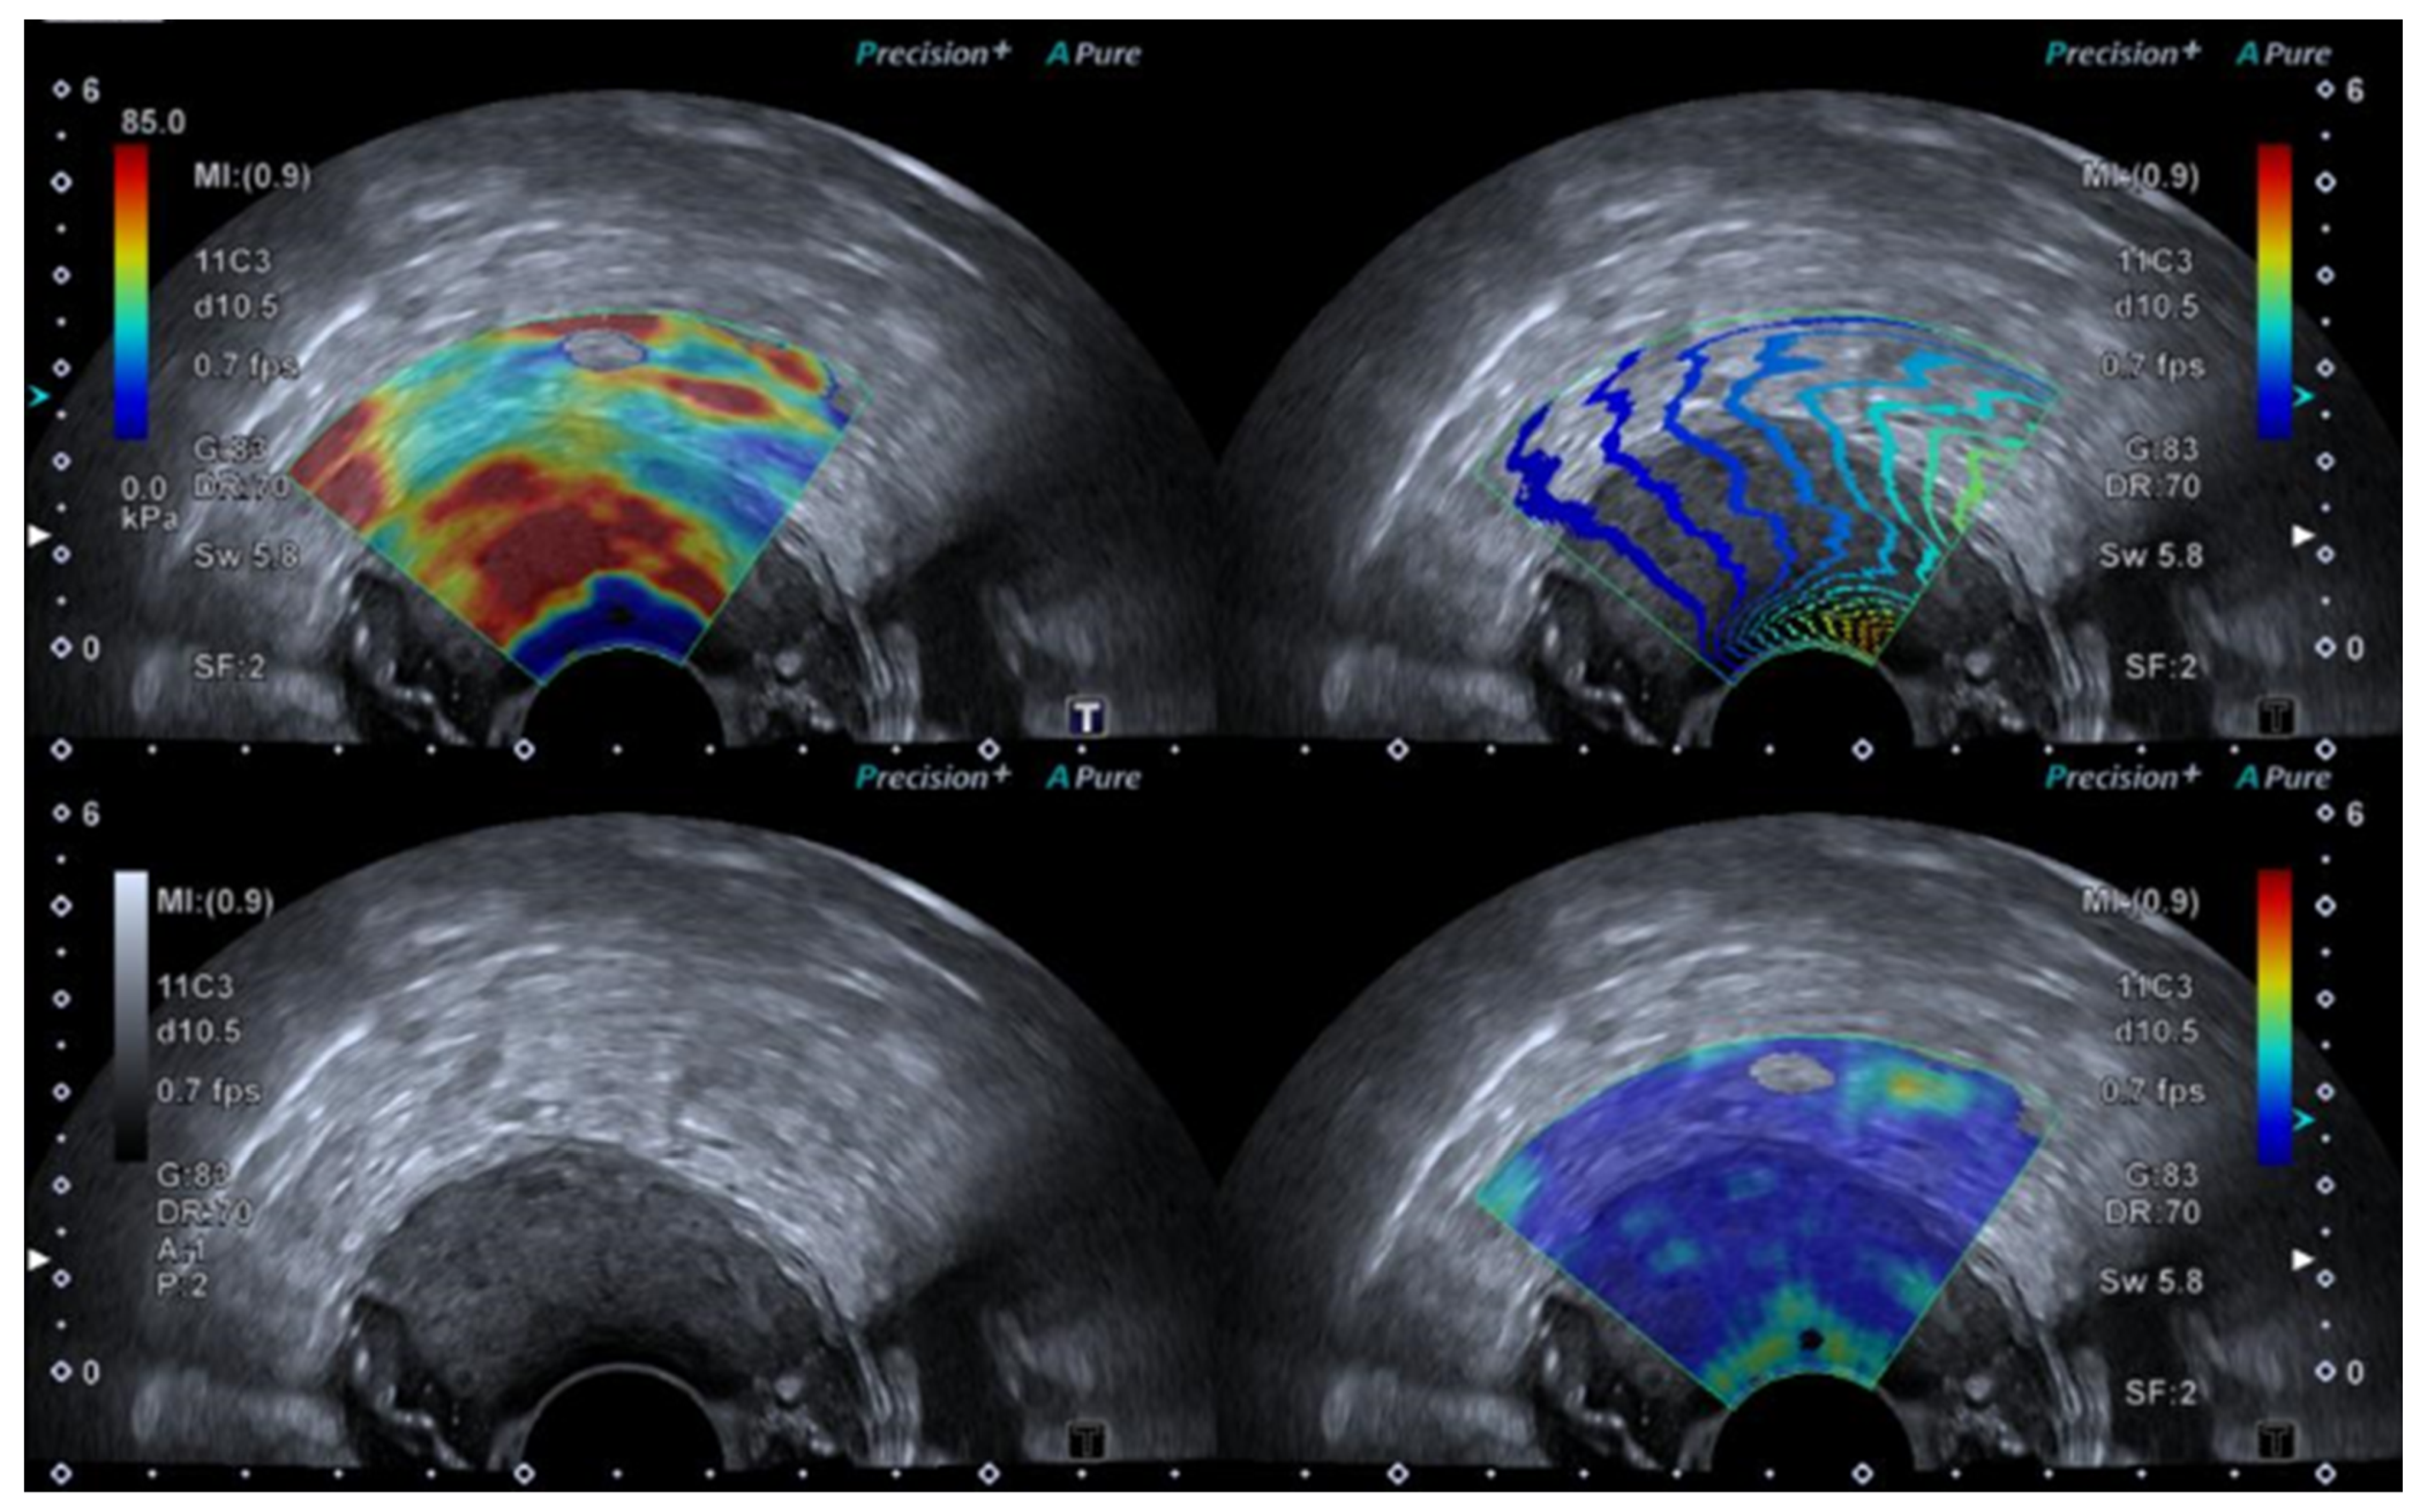

Figure 2.

SWE ultrasound showing a t3b tumour in a 70-year-old female.

SWE uses a push pulse to induce shear waves, and an elastogram is created by monitoring shear wave speed through the tissue. The transducer is held still, without applying pressure to the tumour area, for approximately 5–10 s until a satisfying elastogram is created on the monitor. A region of interest (ROI) may be placed covering the entire lesion or placed within the stiffest areas of the tumour. The elastography index is reported as either the mean or the maximal value of the ROI. SWE may also be interpreted using a visual colour scale [29,30,31,32].

Several cut-off values have been suggested for both SE and SWE (see Table 1); however, it is important to keep in mind that the elastography value differs depending on the technical approach, equipment, and software used, as well as intra- and inter-variation between operators.